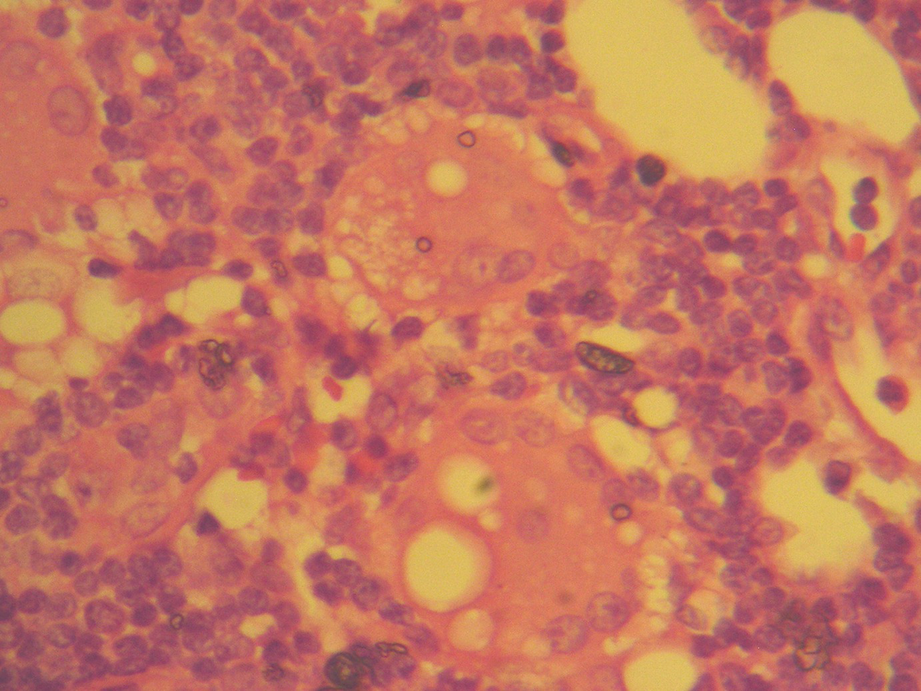

Silicone in the axilla. A lymph node with deposits of silicone and micro-vacuolated histiocytes in the lymphatic sinuses (100× magnification)

Silicone in the axilla. Dilated lymph node sinuses with silicone deposits and micro-vacuolated histiocytes (200× magnification)

Silicone in the axilla. Silicone lumps and micro-vacuolated histiocytes in lymph nodes (450× magnification)

Silicone in the axilla. Silicone lumps in lymph nodes (450× magnification)